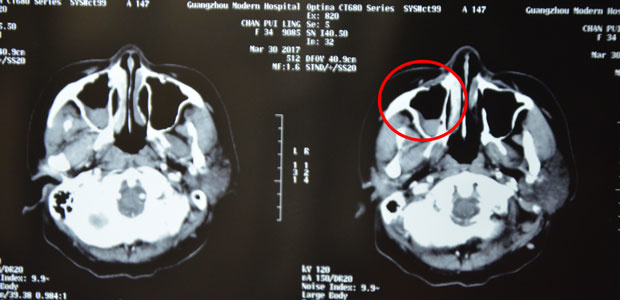

Before treatment and after the first interventional therapy

In Feb. before treatment, masses filled her nasal and sinus cavities and her right eyeball was pressed to displace.

In March, after treatment, masses in her nasal and sinus cavities reduced and basically returned to a normal stage and her right eyeball back to the position.